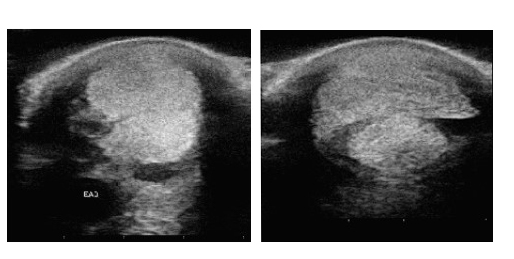

Campos MJ, Agüera EI, Requena F. Córdoba, Spain, March 2020. 세포생물학, 생리학, 면역학과, 코르도바 대학교 연구박사 ” 448KHz 수용성/저항성 단극성 고주파를 말의 등간 힘줄 병리학에 사용”.

4주간 8회 세션 치료

치료 전

치료 후